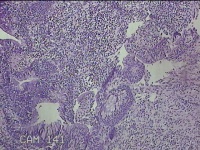

右侧鼻腔新生物

性别

女

年龄

37岁

临床诊断

1.慢性鼻窦炎 2.鼻腔新生物 3.变应性鼻炎

一般病史

鼻塞、脓涕1月。

标本名称

大体所见

灰白暗红色肿物1.3x0.7x0.3cm一个,表面光滑,切面灰白粉红色,质软。